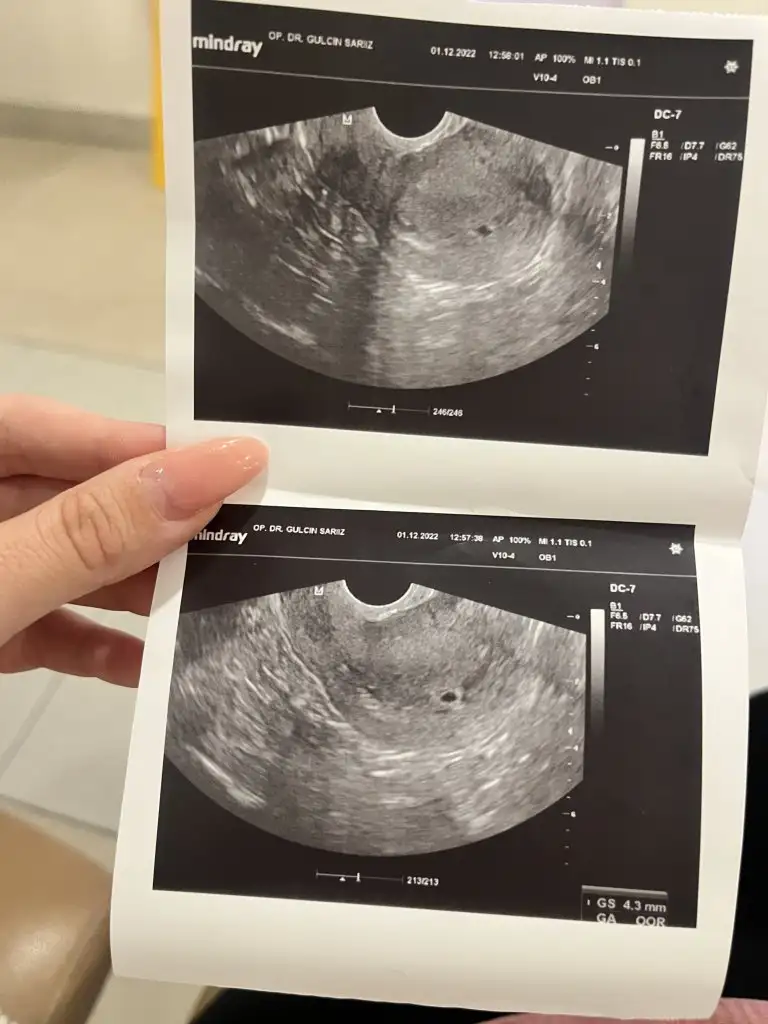

Ben bugün doktora gittim, üstten bakıldı. Kese göremedi. Hafta içi tekrar gel bakalım dedi. Umarım haftaya görebilirizBetam da iyiydi aslında, umarım cihazdan falandır

Bekliyoruz o zaman güzel haberleri. Sizin muayenede karından mı gördü?kızlar 28 kasımda beta 1850’di

Ne guzel darisi bizlerin başına insallahKarından net görünmedi alttan baktı görüldü ama çok küçük henüz dedi takip edelim dedi enerjisi iyi geldi diğer doktora göre daha açıklayıcı

Peki betana baktı mı? Senin mini mini minnak keseni severim benKarından net görünmedi alttan baktı görüldü ama çok küçük henüz dedi takip edelim dedi enerjisi iyi geldi diğer doktora göre daha açıklayıcı